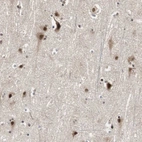

Immunohistochemical staining of human cerebral cortex shows strong nuclear positivity in neuronal cells.